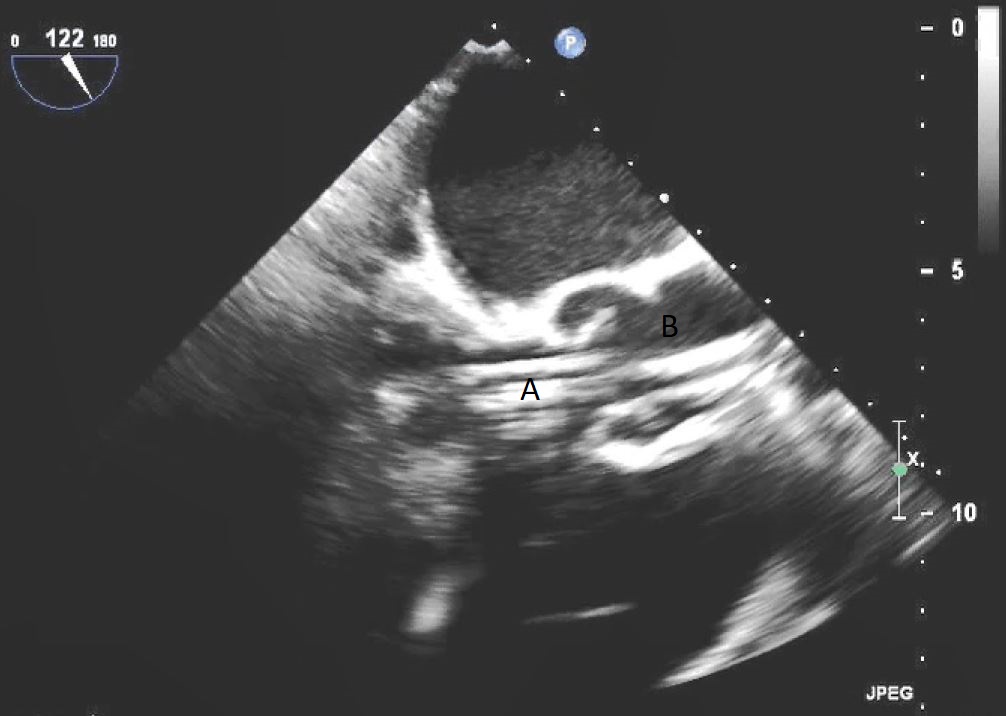

The intra-aortic balloon pump is a percutaneously placed counter pulsation device which helps in decreasing afterload as well as augmenting coronary perfusion. Initially developed in the 1960s it is the oldest MCS device and given its simplicity, cost effectiveness, and ease to implant and explant, it is the most commonly used temporary support device [6]. Although it is typically placed in the cardiac catheterization lab under fluoroscopic guidance, TEE can be utilized to help in its placement in the intubated patient in the intra-operative setting. The femoral artery is the most common site of placement however they can on occasion be placed in alternative sites such as the axillary artery or directly into the aorta [7, 8]. When placed via the femoral artery, it is threaded over a guidewire. TEE can be used to visualize both the guidewire as well as the tip of the IABP catheter during placement (Fig. 1) [9]. Ideal positioning of the balloon tip is 1–2 cm distal to the left subclavian artery to derive maximal hemodynamic benefit [10]. Positioning can be confirmed by visualizing the descending aorta and then withdrawing the TEE probe until the left subclavian artery and aortic arch are visualized. Upon activation of the balloon pump the gas filled balloon will cause shadowing and reverberation artifacts (Fig. 2). Its presence can be used as confirmation of proper function of the device. If these artifacts are not seen or bubbles are visualized in the aorta, rupture of the IABP should be suspected [9]. In addition to hemodynamic monitoring with a Swan-Ganz catheter, TTE can be used to monitor LV function after IABP placement and can help guide weaning of IABP support. It can also visualize any new or worsening aortic regurgitation. Given that IABPs work by reducing afterload, on rare occasions they can precipitate dynamic outflow tract obstruction and paradoxically worsen cardiogenic shock. Examples include patients with a relatively preserved basal or septal myocardial function in scenarios such as takotsubo cardiomyopathy or acute myocardial infarctions. Doppler imaging and color flow doppler can be used to identify such scenarios [11].

Fig. 1.TEE demonstrating IABP in descending aorta (A).

TEE demonstrating IABP in descending aorta (A) with reverberation artifact seen behind it upon activation (B).